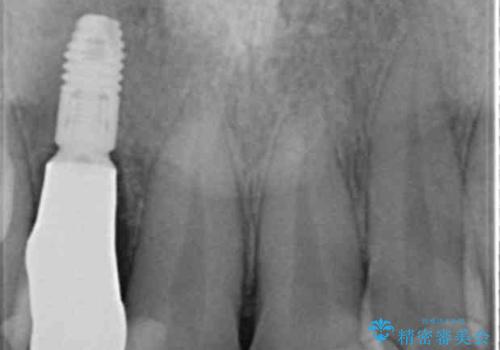

- 虫歯の治療を繰り返した前歯の見た目の改善を求めて来院されました。

大きく詰められたコンポジットレジンと虫歯の再発が見られ、経年劣化により審美性も損なわれていました。

充填されたコンポジットレジン・再発した虫歯を神経に影響が出ないよう丁寧に除去し再充填をしたのちオールセラミッククラウンで前歯の審美性を回復します。

※右上2のインプラント治療は他院のものです。